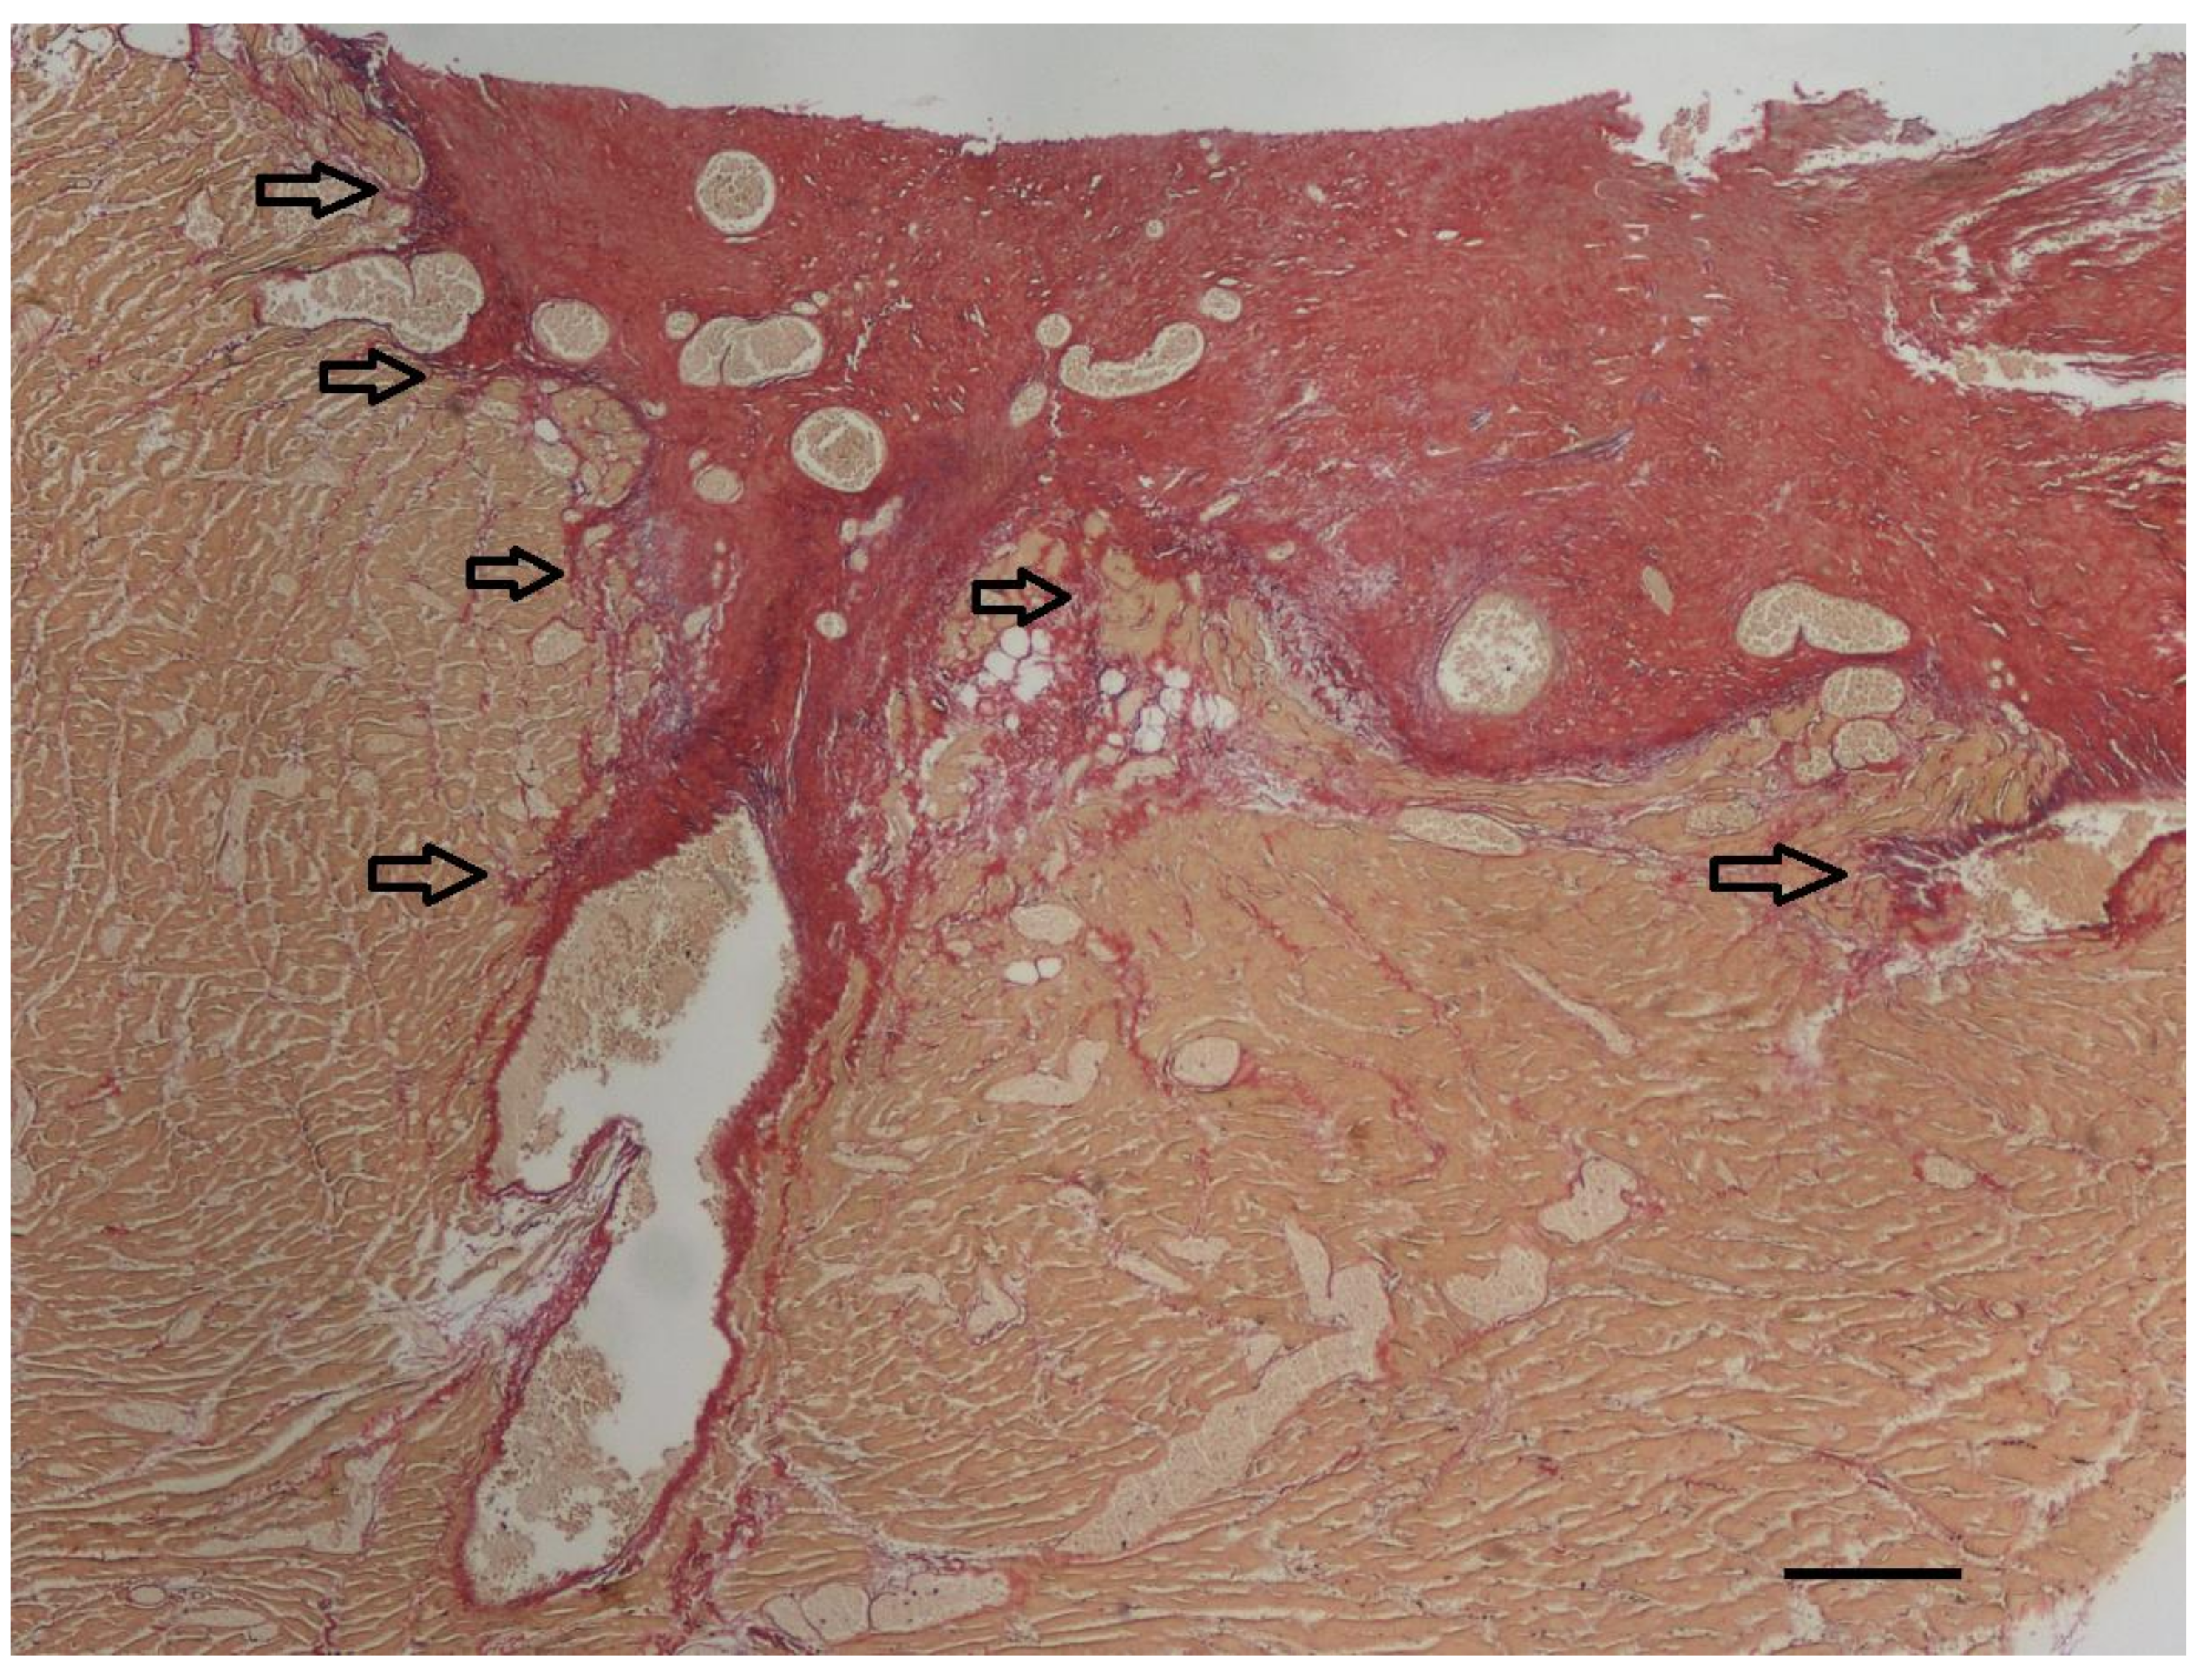

Histopathologic examination was performed on representative sites of the heart. The localized right ventricular muscular hypertrophy was composed of whirly arranged cardiomyocytes (Figure 7). Modified picrosirius red stain revealed severe focal endocardial fibrosis at the muscle bundle infiltrating the underlying right ventricular myocardium (Figure 8). The endocardium, myocardium, and pericardium, as well as the great vessels, were normal. The pulmonary alveolar septae showed mild fibrosis but no hemosiderin-loaded macrophages.

The exact mechanism of how mid-ventricular septation develops is uncertain. Various theories exist. One suggests that hypertrophy of abnormal septo-parietal trabeculations can lead to DCRV [8]. Another theory suspects that infundibular stenosis is the primary lesion consisting of obstructive fibrous muscle bands at the junction of the main right ventricle and the proximal infundibulum [8]. Because in more than 90% of the humans with DCRV a subaortic VSD is present, the high-pressure jet, i.e., turbulent flow, caused by the left-to-right shunting blood through the VSD is thought to play a role in the genesis of the right ventricular muscular hypertrophy and fibrous tissue formation due to shear stress [7,8]. A recent study in humans showed that the responsible mechanism that contributes to the septation of the right ventricle is an invasive fibroelastic remodeling process of the endocardium into the underlying myocardium through activation of endothelial-to-mesenchymal transition [8]. This mechanism is also a physiologic process described in the embryologic development of heart valves [8]. For the development of DCRV, an underlying anatomical substrate, such as an abnormal congenital muscle bundle, is thought to be required. Turbulent blood flow caused by this bundle and/or flow via a left-to-right shunting VSD can result in shear stress, and in turn localized fibrotic remodeling, and progressive worsening of the right ventricular septation [7,8]. The histologic findings in the presented dog were very similar to those reported in humans, which suggests a similar pathogenesis [8]. In the specimen of the presented dog, histopathology of the abnormal muscular band revealed a large amount of subendocardial fibrosis and infiltration of the underlying myocardium with collagen originating from the surface, similar to that described in humans. Modified picrosirius red stain stains not only collagen but also elastic fibers. In the presented specimen, the elastin content was only minimally increased, and it was not as obvious as it is described in human specimens of DCRV or in hearts with endocardial fibroelastosis [8]. A possible explanation for this finding can be differences in species-specific reaction patterns. Another possible explanation is that endothelial-to-mesenchymal transition in dogs is perhaps not a (major) mechanism in the development of DCRV. Because not every left-to-right shunting VSD results in a DCRV, an underlying substrate in the right ventricle, like an abnormal congenital muscular bundle, is most likely present in patients with the Gasul phenomenon [4,8].

Figure 8. At the endocardial side of the longitudinal section of the right ventricular muscular hypertrophy (yellow), severe focal endocardial fibrosis (red) is present. The arrows indicate infiltration of collagen into the underlying myocardium. In addition to the thick subendocardial layer of collagen, collagen also surrounds the diffuse myocardial bundles throughout the underlying myocardium. Only a minimal increase in elastin fibers (violet) can be appreciated in this specimen accompanying the collagen fibers (red). Modified picrosirius red stain, bar = 200 µm.